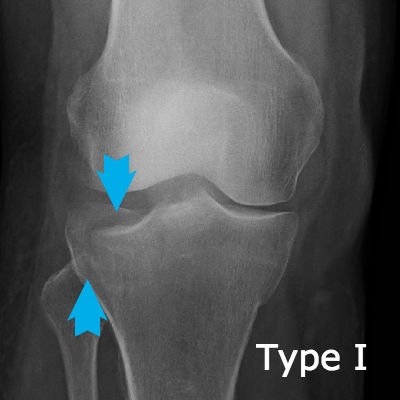

Tibial plateau fractures are very significant because the break goes through the joint line and upsets the dynamics of the joint. This X-ray shows a Schatzker Type I fracture.